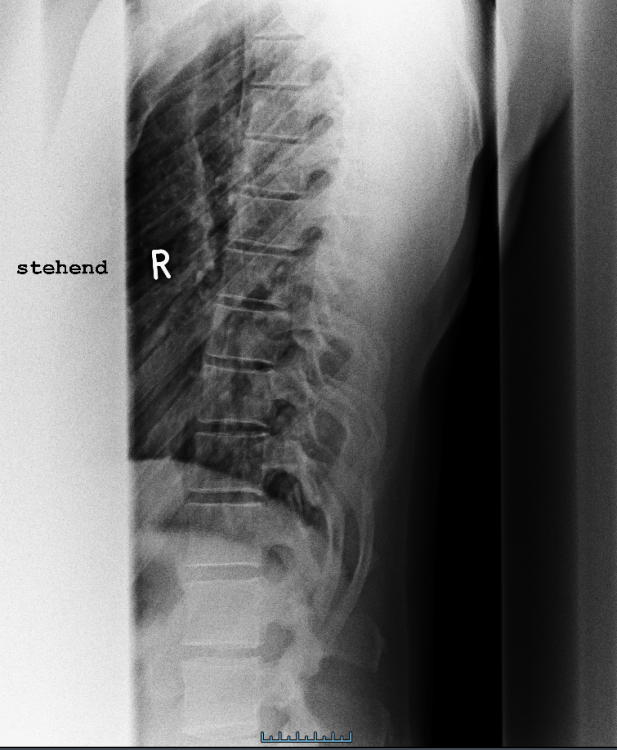

Ich weiß aus der Vergangenheit, dass ich eine fehlende Lordose in der LWS, eine fehlende Kyphose in der BWS und eine fehlende Lordose in der HWS habe. Dies wurde vor 2 Jahren auch durch eine Röntgenaufnahme bestätigt. Seit einigen Monaten arbeite ich zudem an der Verbesserung meiner Haltung. Durch meinen Physiotherapeuten wurde mir damals gesagt, ich solle meine Hamstrings sowie den Hüftbeuger dehnen. Seit ich mich jedoch mit der Materie etwas beschäftige, bin ich etwas verwirrt. Meines jetzigen Wissens nach, kommt eine fehlende Lordose in der HWS vor allem durch eine Verkürzung der Beinrückseite sowie des Bauches und einer Inaktivität der Hüftbeuger sowie des unteren Rückens.

Ich habe hier einmal die Röntgenbilder der LWS und BWS sowie den MRT Befund beigefügt. Ich bin mir durchaus bewusst, dass ein fachärztlicher Rat natürlich genau ratsam ist wie eine persönliche Vorstellung bei eben jenem, allerdings war ich wie gesagt, bereits bei etlichen Ärzten und noch möchte ich versuchen, einer künstlichen Bandscheibe aus dem Weg zu gehen.

BWS seitlich.png